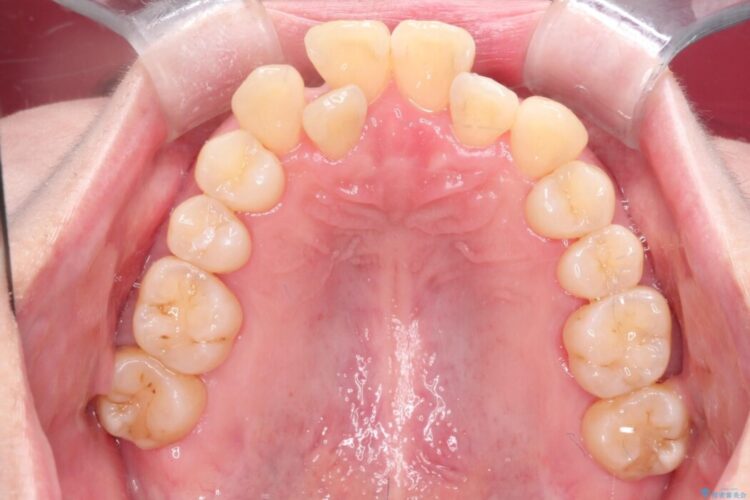

検査をしたところ噛み合わせのズレに加えて歯周病も併発していました。

ガタガタだった前歯も整いきれいなアーチとなり、噛み合わせも改善されました。